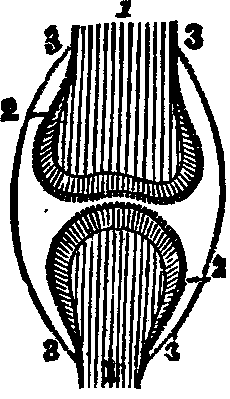

Fig. 4. Nucleated cell.

From Goeber. 1. Periphery of the cell, or cell-wall. 2. Nucleus. 3.

Nucleolus in the center.

A variety of tissues enters into the composition of an animal structure, yet their differences are not always distinctly marked, since the characteristics of some are not unlike those of others. We shall notice, however, only the more important of the tissues.